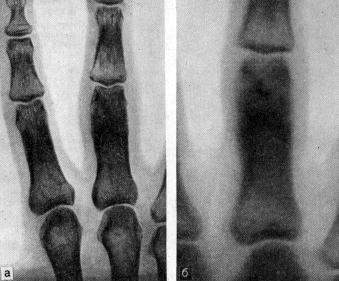

Остеоид-остеома на рентгенограмме

Доброкачественные костные опухоли - доброкачественные новообразования, которые вызывают боли и деформацию костей. Чаще поражают детей и подростков, очень редко - взрослых после 40 лет. Пол, генетика, образ жизни значения не имеют.

Доброкачественные костные опухоли могут поражать любые кости. Чаще всего они развиваются в трубчатых костях конечностей, например бедренных, также часто - в костях кистей рук.

Костные опухоли обычно диагностируют по рентгеновским снимкам, магнитно-резонансным или радиоизотопным сканам. Для подтверждения нераковой природы опухоли врач проводит биопсию обраца костной ткани.